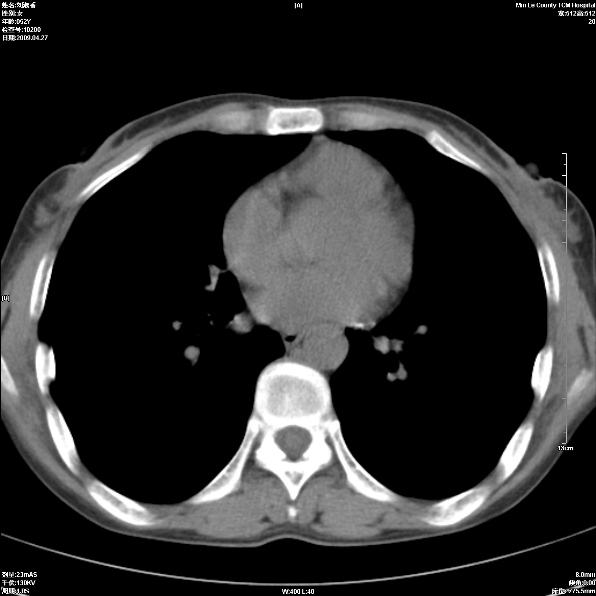

标题: CT19625:女52间断性喀血 [打印本页]

标题: CT19625:女52间断性喀血

考虑右肺中叶感染性病变并右肺中、下叶肺泡积血;建议抗炎、止血治疗后复查。

右肺中叶炎症;右肺中、下叶肺泡积血

考虑 右肺中叶感染性病变伴右肺中下叶肺泡积血。

右肺中叶支气管扩张并感染或咳血沉积,块右肺中下叶肺泡积血。

右肺中叶慢性炎症伴局部支扩并中下叶肺泡积血。

考虑右肺中叶感染性病变并右肺中、下叶肺泡积血。建议治疗后复查。